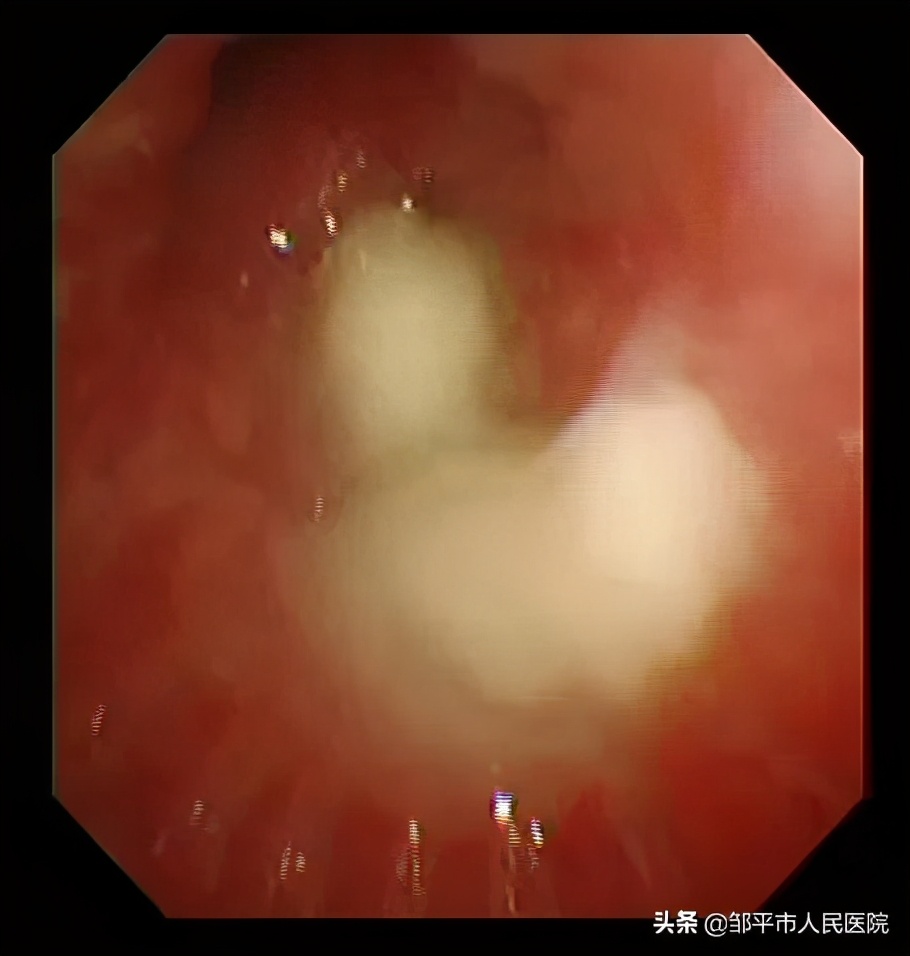

儿二科副主任张鲁渤协同麻醉科、内镜中心团队,用新引进的儿童超细电子支气管镜对患儿进行了支气管检查,发现多个支气管分支处有大量黄白粘痰附着,这就是肺炎、肺不张的“罪魁祸首”。通过肺泡灌洗。很快就把这些粘痰清除干净了。

清洗前